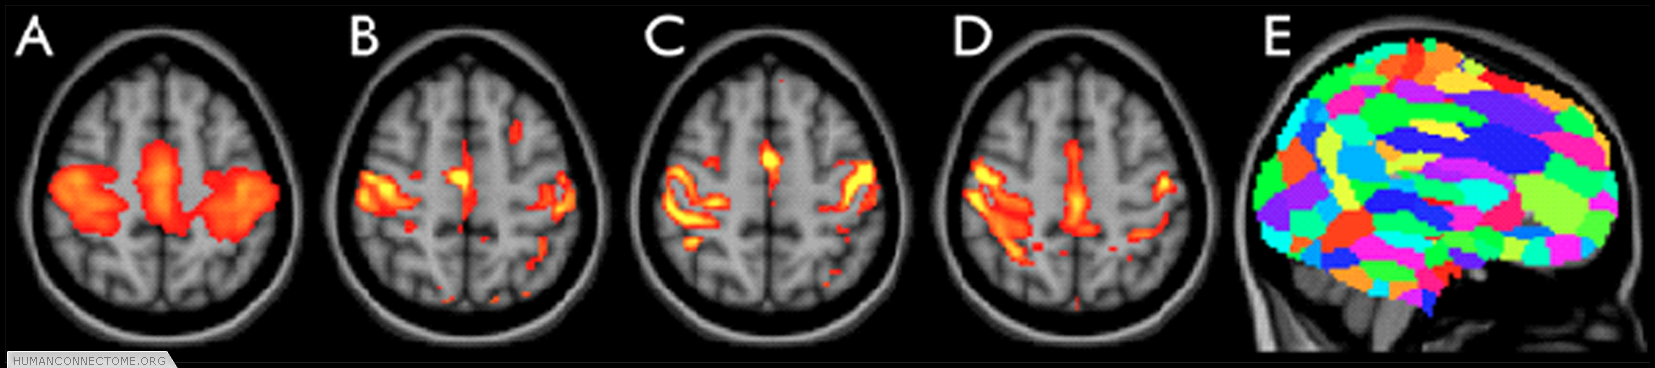

Figure 2: ICA-based parcellation of 3T resting-FMRI data. (A) group-mean parcellation of a primary sensori-motor region (one “resting state network”). (B-D) The corresponding map from 3 different subjects, achieved by applying “dual regression” of the group map into each individual data set. (E) Whole-brain parcellation resulting from applying ICA to the group data and combining across all ICA components.